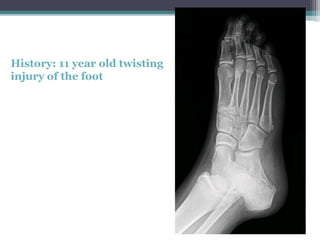

History: 11 year old twisting

injury of the foot

History: 11 yearold twisting injury of the foot